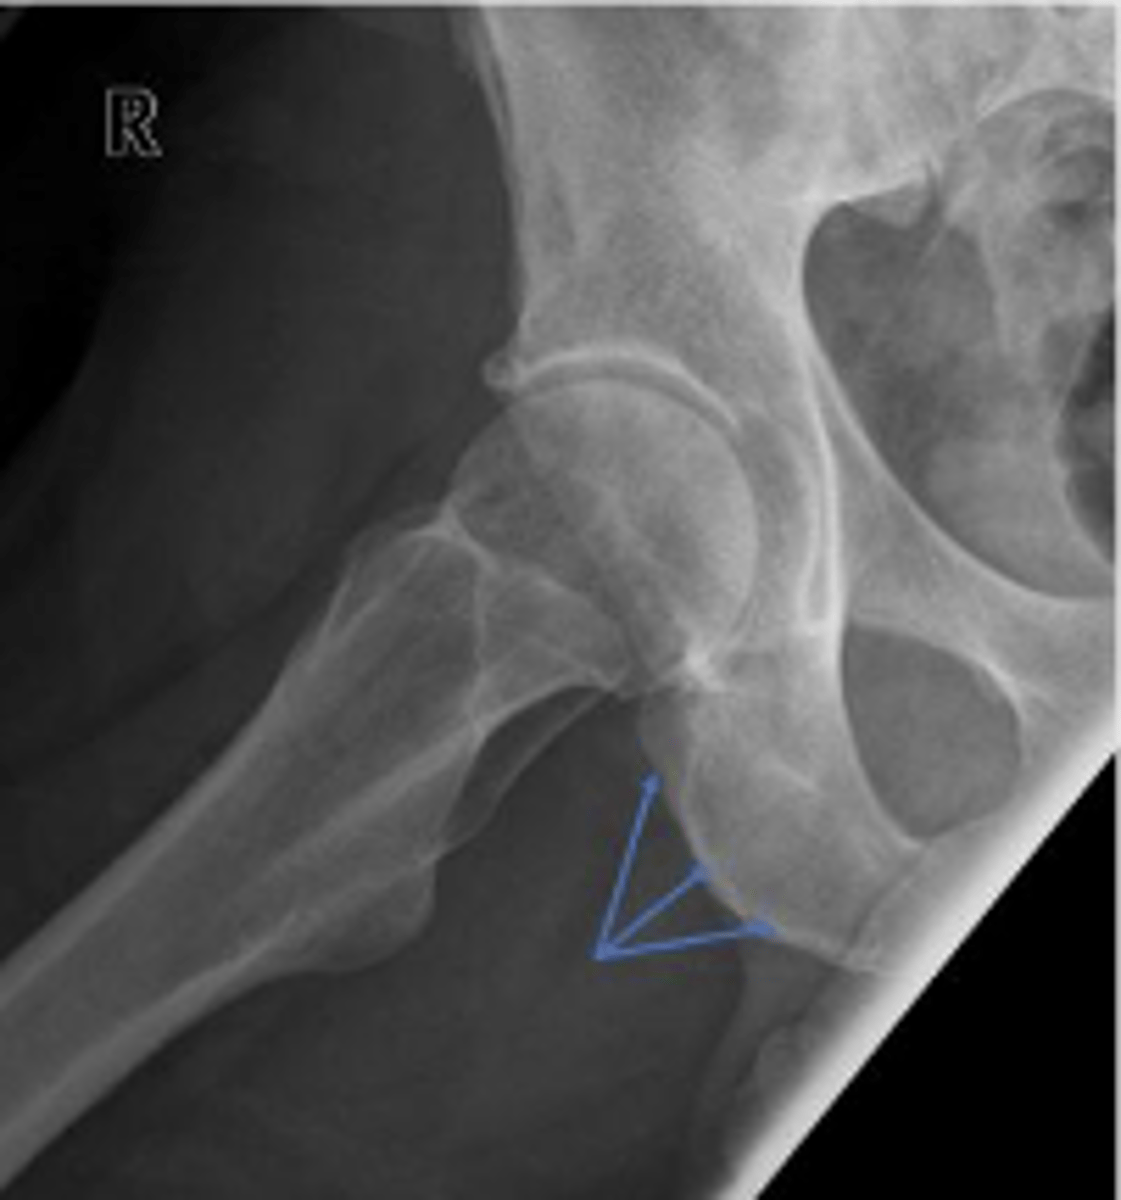

Right AP hip

What is the name of the radiographic view?

Posterior rim of the right acetabulum

What are the arrows pointing to?

Anterior rim of the right acetabulum

Lesser trochanter of the right femur

Greater trochanter of the right femur

Right posterior inferior iliac spine

Intertrochanteric line of the right femur

Right ischial tuberosity